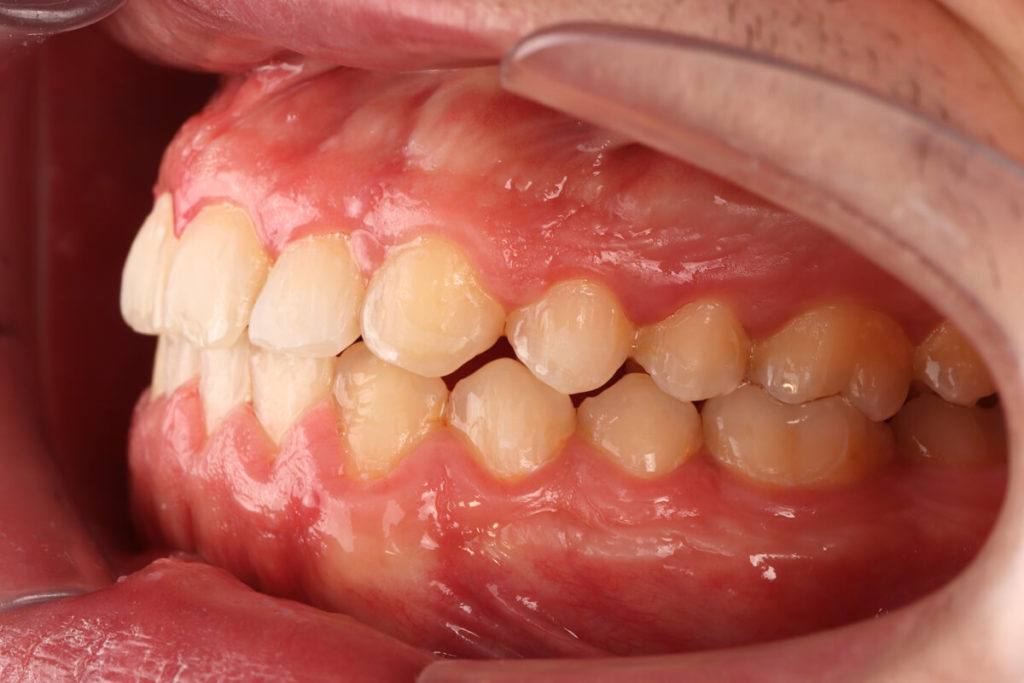

SITUACIÓN INICIAL

CLASE I MORDIDA CRUZADA EN LATERALES

• Clase I con mordida cruzada en los incisivos laterales.

• Apiñamiento moderado en el arco superior e inferior.

• Desplazamiento de la línea media superior.

• Arco normal con necesidad de expansión.